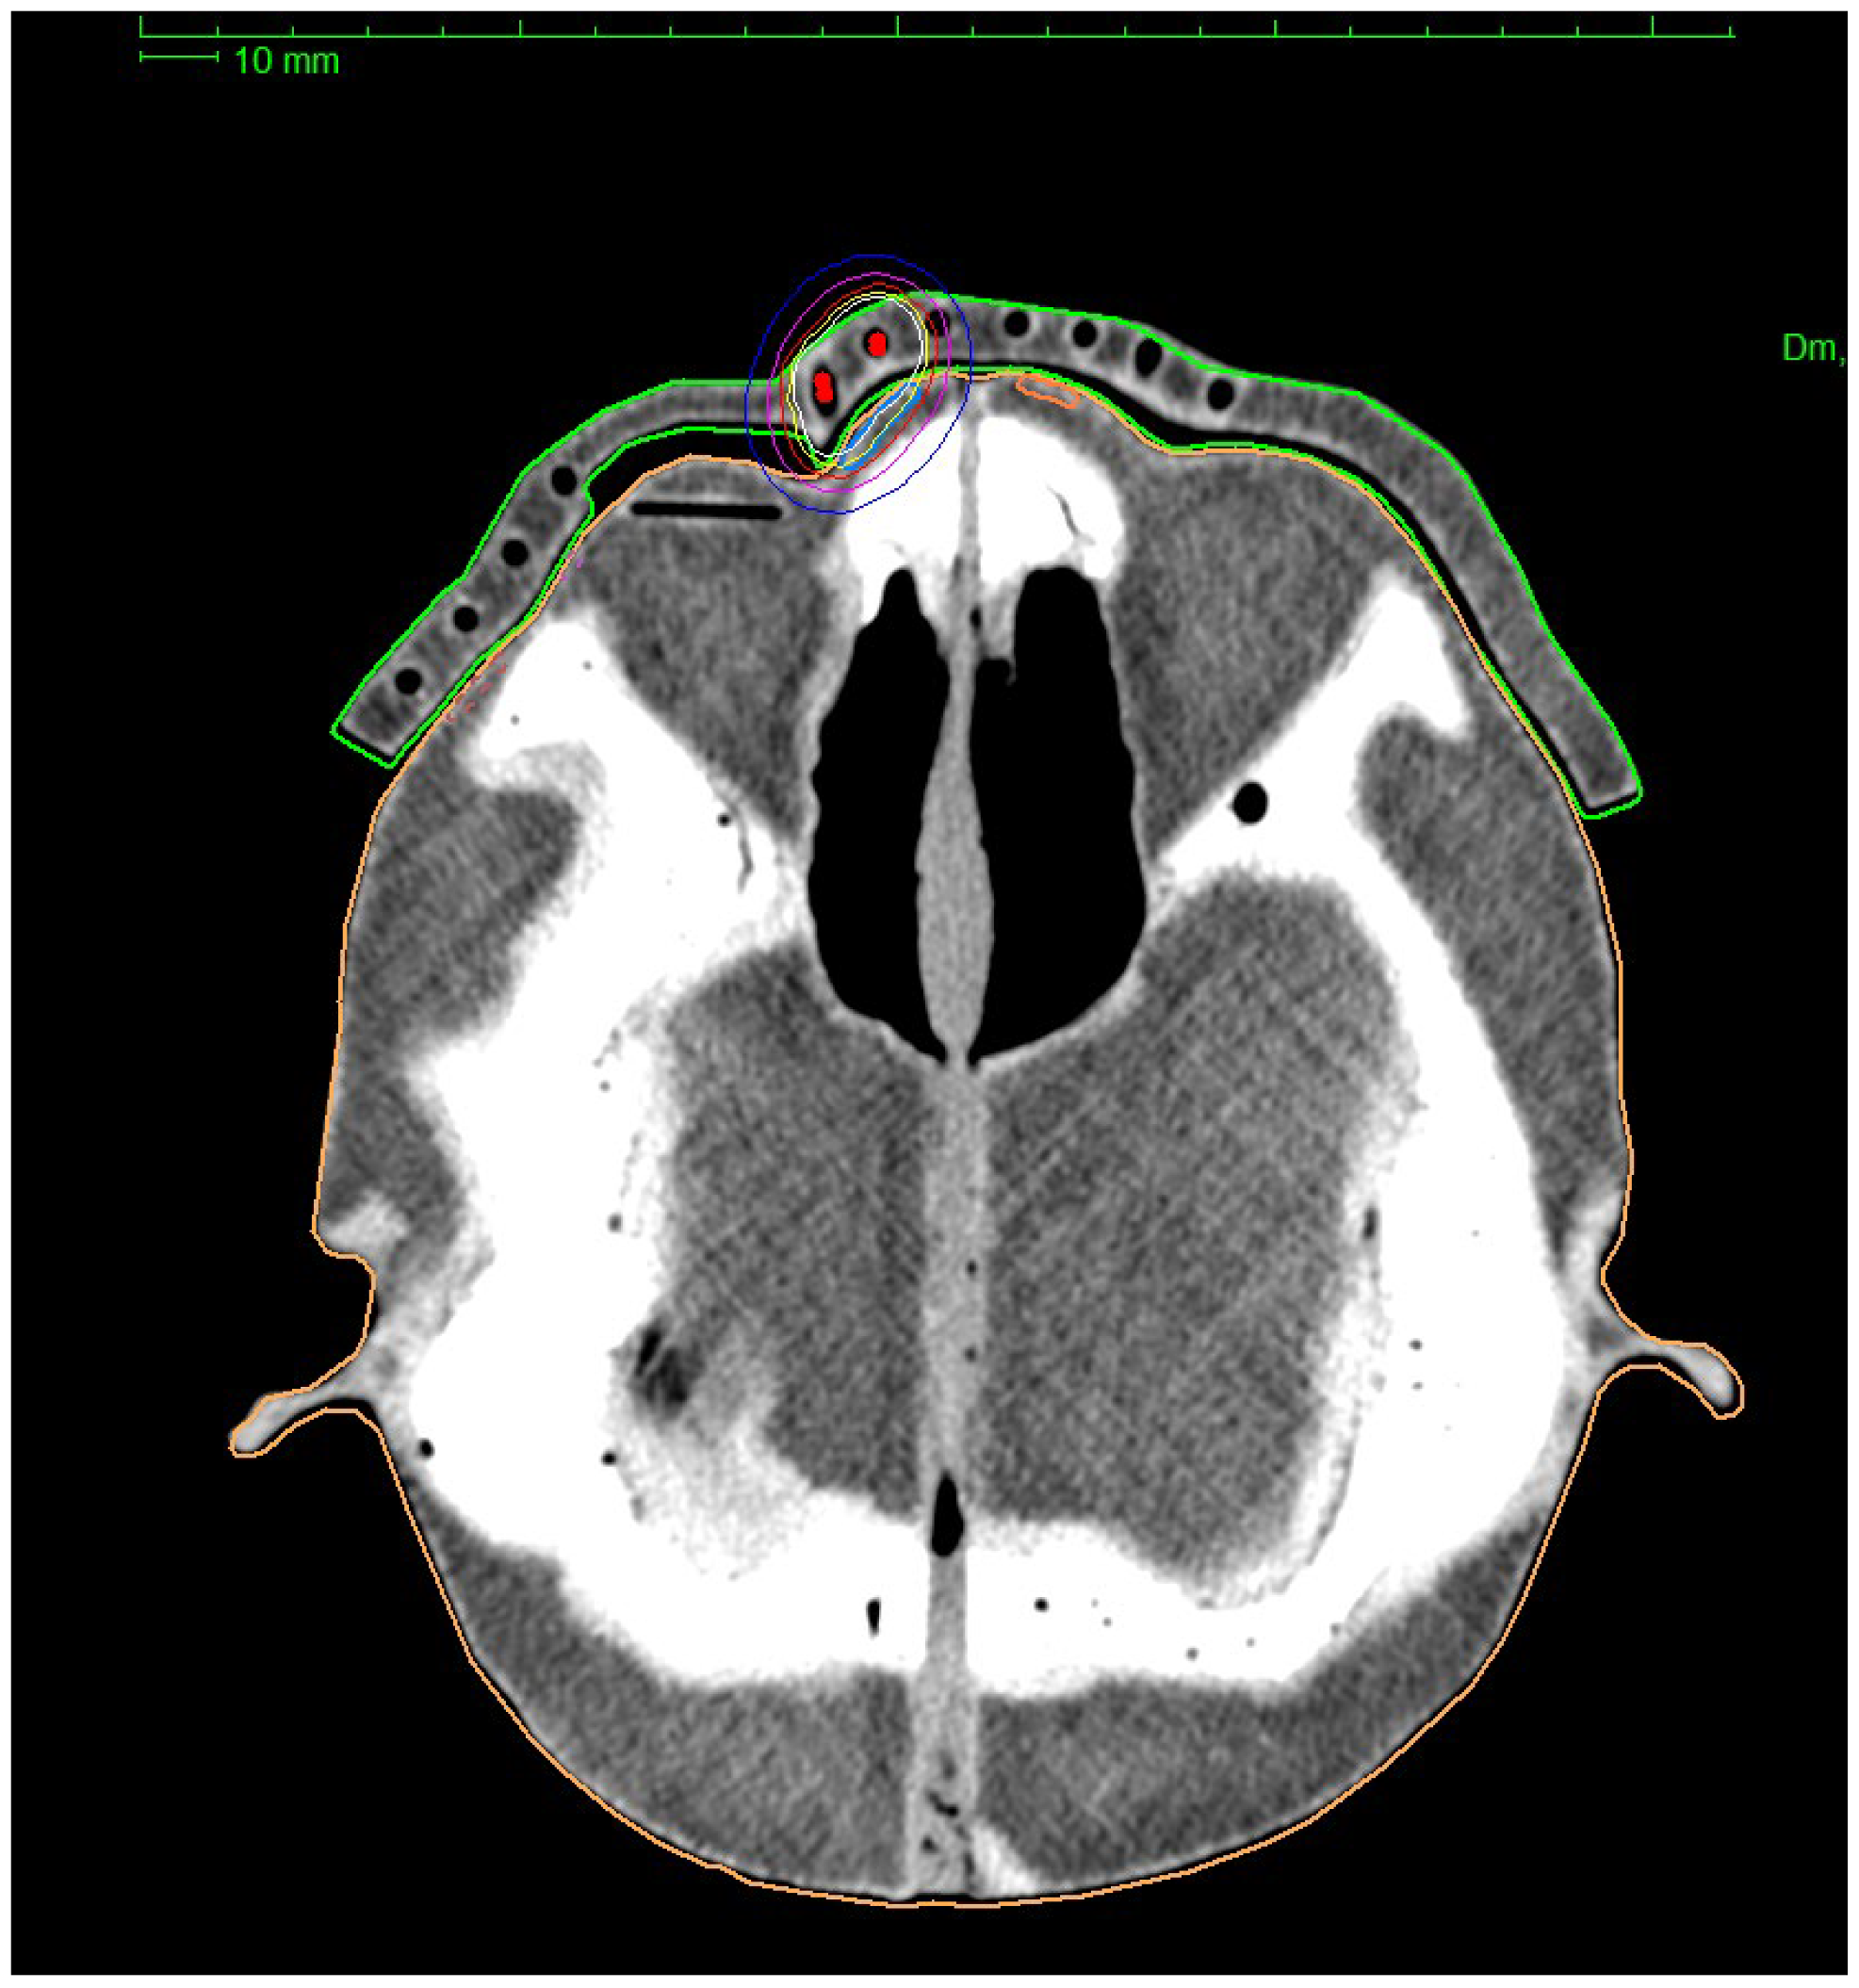

A custom-printed personalized surface applicator was used to perform the phantom simulated treatment. The design of the custom applicator was based on CT images of the head phantom taken with 1 mm layers separation. The resulting images were imported into the OncentraBrachyTM treatment planning system. The first step was to determine the outer contour of the phantom, using the lung window (width of 1600 HU with center at −600 HU). Using such settings allows to prepare an applicator that fits well on the facial surface. Using the transverse CT images, 10 sample target areas (CTV 1–10) were delineated on the facial surface, which were located at different linear and angular distances from the right eye. A bolus of 1 cm was then added to the outer contour of the patient at eye level. The added volume covers the area where the target volumes were located. The prepared bolus on the surface of the phantom outline is shown in Figure 3. At the height of the right eye, a space 2 cm wide and 0.5 cm deep was prepared to allow the lead shield to be inserted into the applicator.

Using the treatment planning system, 14 channels for the source, spaced 0.5 cm from the skin surface and 1 cm from each other were designed. To create the channels in the applicator, a structure representing the volume of the applicator itself (RTStructure) was first exported to the BebenTM program. Using the exported RTPlan file, the catheter paths inside the applicator were generated. The RTPlan file contains the coordinates of the source’s active stop positions in the same coordinate system as the coordinates of the applicator vertices. To ensure collision-free source insertion, the diameter of the channels was set at 3 mm. The applicator with channels for catheters and with space for the lead shield is shown in Figure 4.

In order to finally prepare the treatment plan, the head phantom along with the 3D applicator fixed (Figure 5.) was imaged using a CT. The volumes of the critical organs and the target volumes were determined on the obtained images.

Using image fusion, the outlines of the eyes, lenses, and bones of the real patient were superimposed on the CT images of the phantom. In this way, it was possible to accurately delineate the critical organs in the CT cross sections of the printed phantom. Then the source travel paths in all channels of the designed applicator were reconstructed in the treatment planning system.

For the purpose of this study 10 target areas located at different distances from the right eye were determined. They were located: on the right temple (CTV 1), in the outer corner of the right eye (CTV 2, CTV 3), under the eye (CTV 4), in the inner corner of the right eye (CTV 5, CTV 6, CTV 7), on the tip of the nose (CTV 8), and near the left eye (CTV 9, CTV 10). Subsequently, 10 treatment plans were created at TPS, for irradiating the corresponding CTV. The treatment plans were carried out in order from 1 to 10. The location of the target areas is shown in Figure 6.